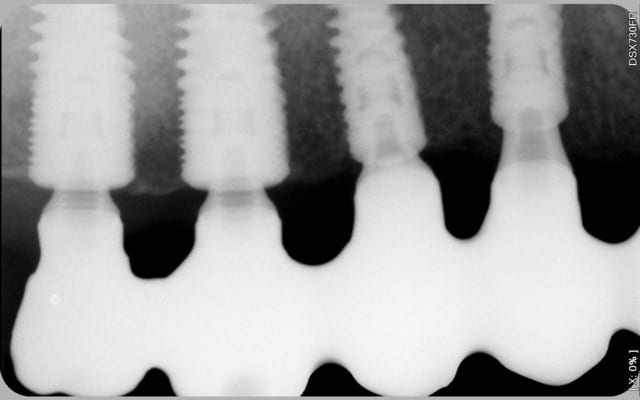

regarde les implants en 13 23 , pour des raisons de conception d'une prothèse transvissée, ils sont posés légèrement en lingual, en dessous de l'os vestibulaire-> la hauteur gingivale est plus importante donc pilier multiunit plus long. je pense que ton cas est exactement le même. tu peut constater que les multiunit sont de longueur différente pour avoir une émergence prothétique de 1mm en sousgingival.